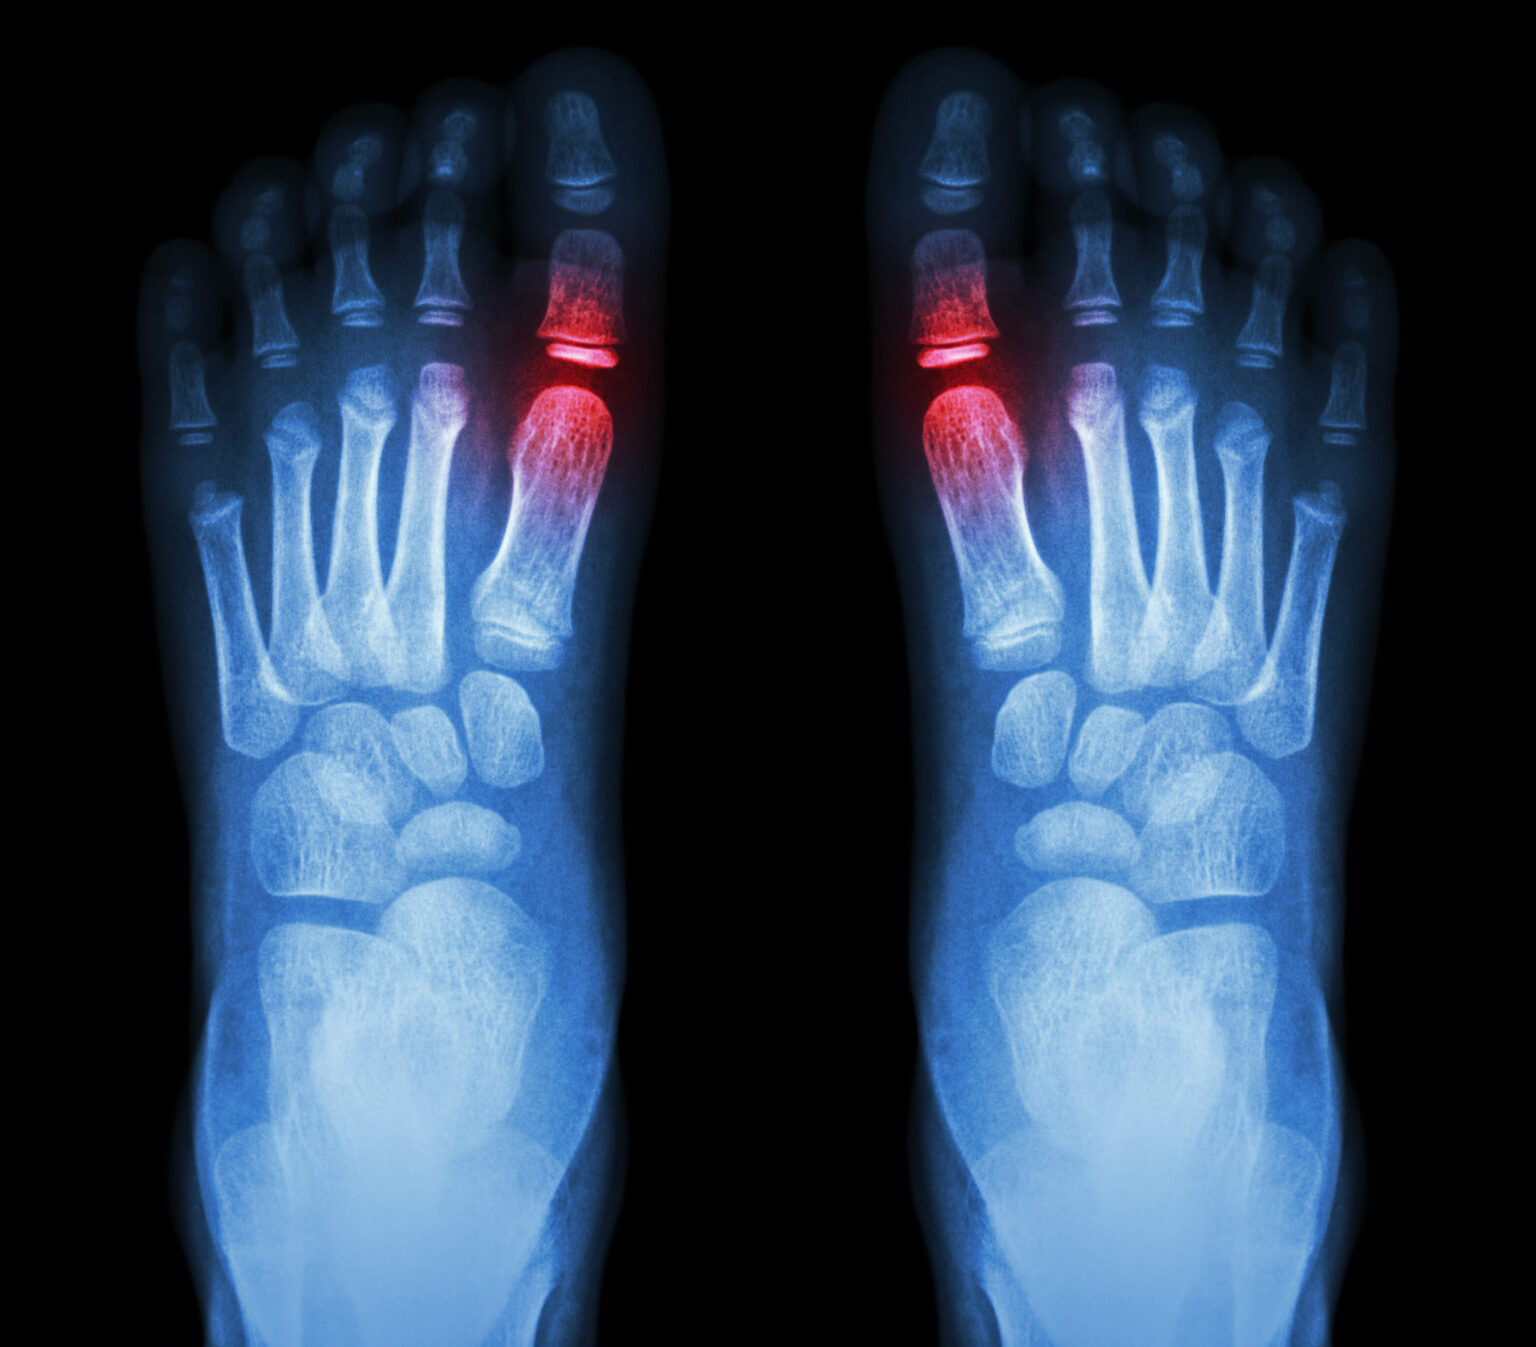

Pain In Bottom Of Toes When Walking . — metatarsalgia involves pain in the ball of the foot. Symptoms of metatarsalgia can include: — however, pain can significantly affect your ability to bear weight through your toes which can limit your ability to comfortably stand and. Sharp, aching or burning pain in the ball of your foot — the. It stems from problems with the metatarsal bones. These are just behind the toes and. — some potential causes of toe pain when walking include:

— metatarsalgia involves pain in the ball of the foot. It stems from problems with the metatarsal bones. Symptoms of metatarsalgia can include: — some potential causes of toe pain when walking include: Sharp, aching or burning pain in the ball of your foot — the. — however, pain can significantly affect your ability to bear weight through your toes which can limit your ability to comfortably stand and. These are just behind the toes and.